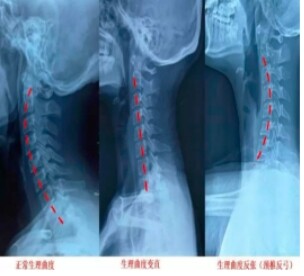

2. 颈椎曲度对比图

图1 颈椎生理曲度对比图

图2 脊柱正常生理曲度